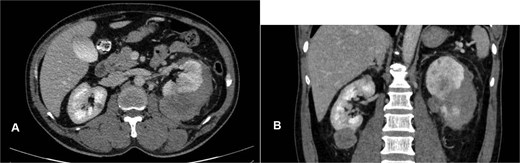

Abdominal ultrasound demonstrated bilateral renal masses and a left subcapsular renal hematoma (Fig. 1). Multiphasic contrast-enhanced computed tomography (CT) revealed multiple bilateral renal tumors with a left subcapsular hematoma, bilateral renal hilar lymphadenopathy, a right retroperitoneal nodule, a mass in the pancreatic uncinate process, and a right adrenal lesion (Fig. 2).

Contrast-enhanced CT showing multiple bilateral renal tumors, a left subcapsular hematoma, a pancreatic uncinate process mass, a right adrenal mass, a right retroperitoneal nodule, and bilateral renal hilum lymphadenopathy.